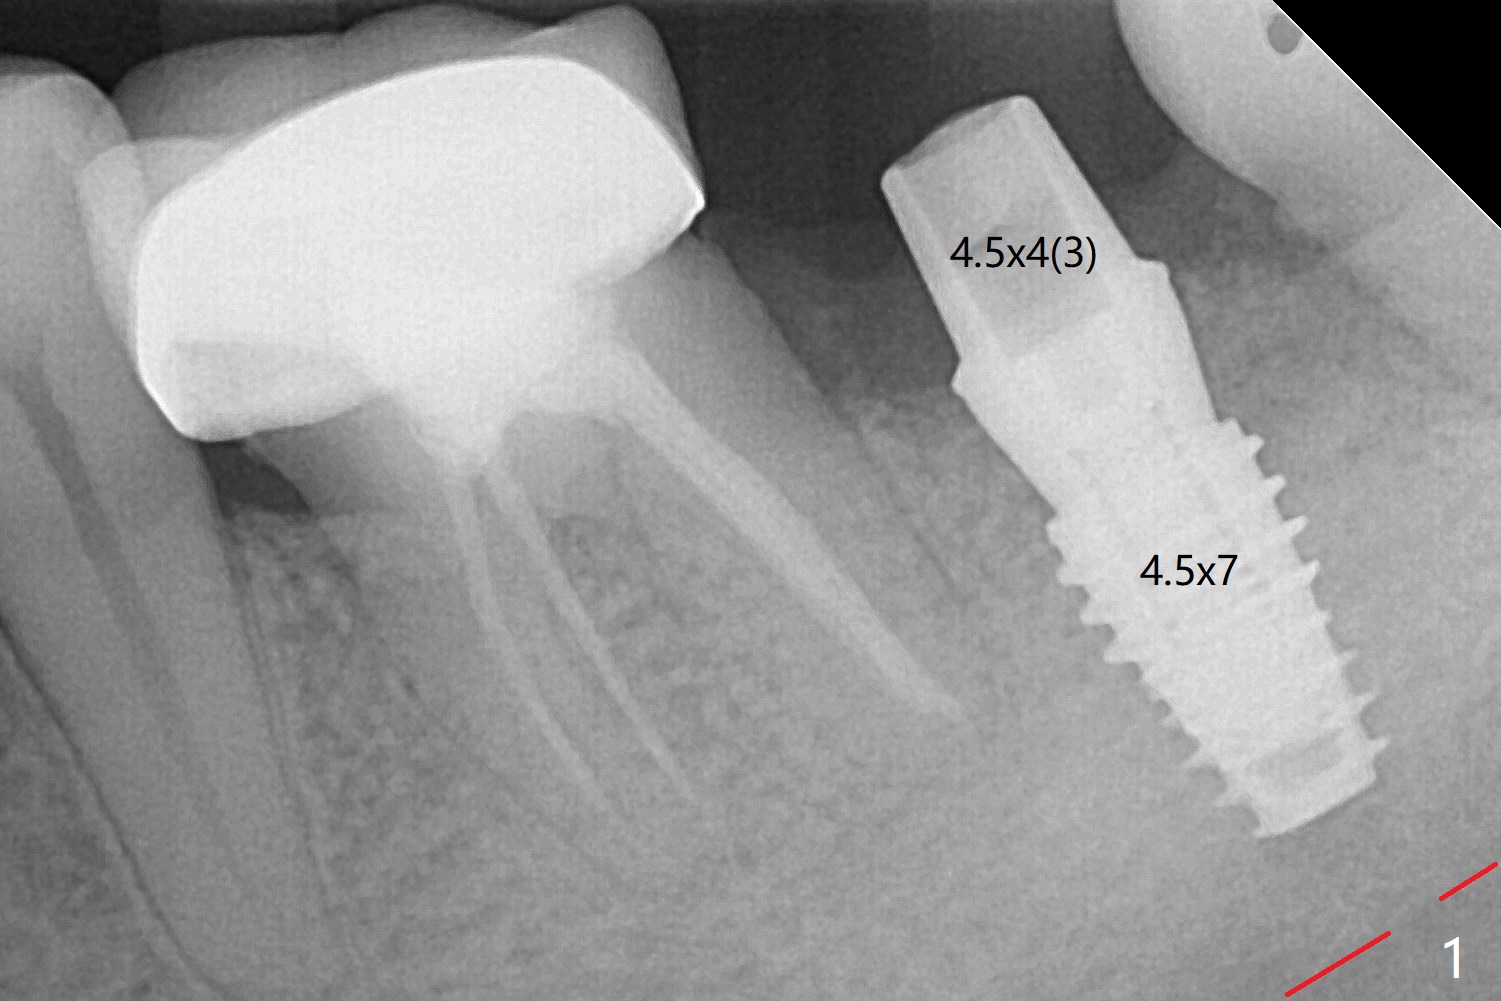

A 4.5x7 mm implant is placed at #31 with >50 Ncm due to the dense bone (Fig.1). The mesiodistal space is so small that a small abutment has to be used (4.5x4(3) mm). Partially because of the dense bone and partially nervousness, the patient feels pain with infiltration during osteotomy. The pain reduces when drill pressure decreases. Bone shaving has to be removed frequently to relieve pressure. PA is taken after the abutment is torqued to 30 Ncm after cleaning (2 months postop, Fig.2). In fact it has to be removed due to subgingival margin and inflamed gingiva. A 5.5x5(3) mm healing abutment is placed.